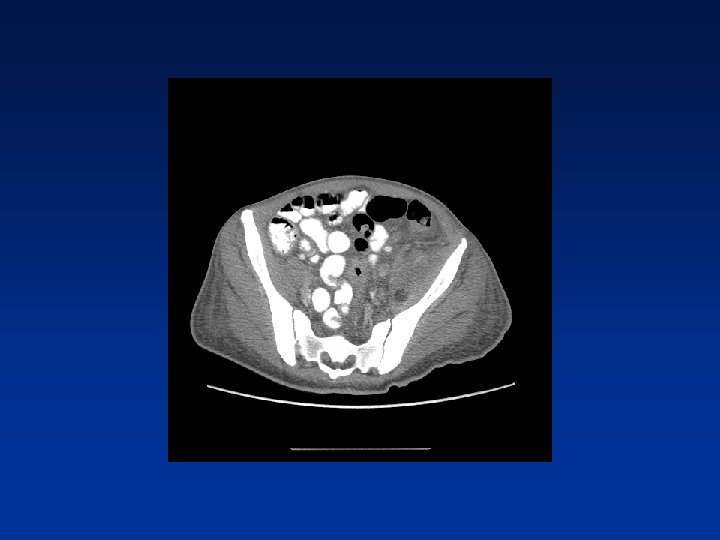

CASE